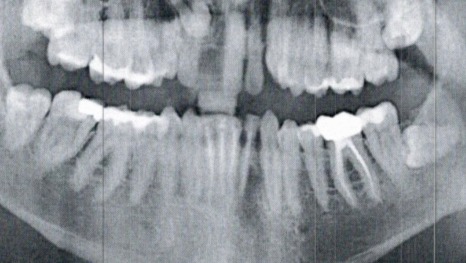

At the time, my family simply did not have the $25,000+ it would have cost to properly repair the damage. I had 11 teeth fractured, and one knocked completely out, along with severe facial trauma. So, we did a band-aid fix, filing my teeth down so they were no longer sharp, and performing root canals on all of them, with the hope that this would buy me 2-4 years of function.

As luck would have it, we managed almost 7, before the problems started catching up to me. A few months ago, I bit into a sandwich, and one of my front teeth fell out. A few months later, another started coming loose. The way it’s looking now, I will go from a jagged smile, to completely toothless by 2026.

There is no hope for the remaining incisors; they are too far gone and have to be removed. Even with insurance, working full-time, and going to a low-cost dental school, I am still looking at a $15,000+ out-of-pocket expense, over the course of two dozen surgeries, that will take approximately 3 years to complete.

(Attached are pictures of my injuries, X-rays, current state of my teeth, and a normal picture of me for reference. It’s gross, be warned lol. Thank you for looking)